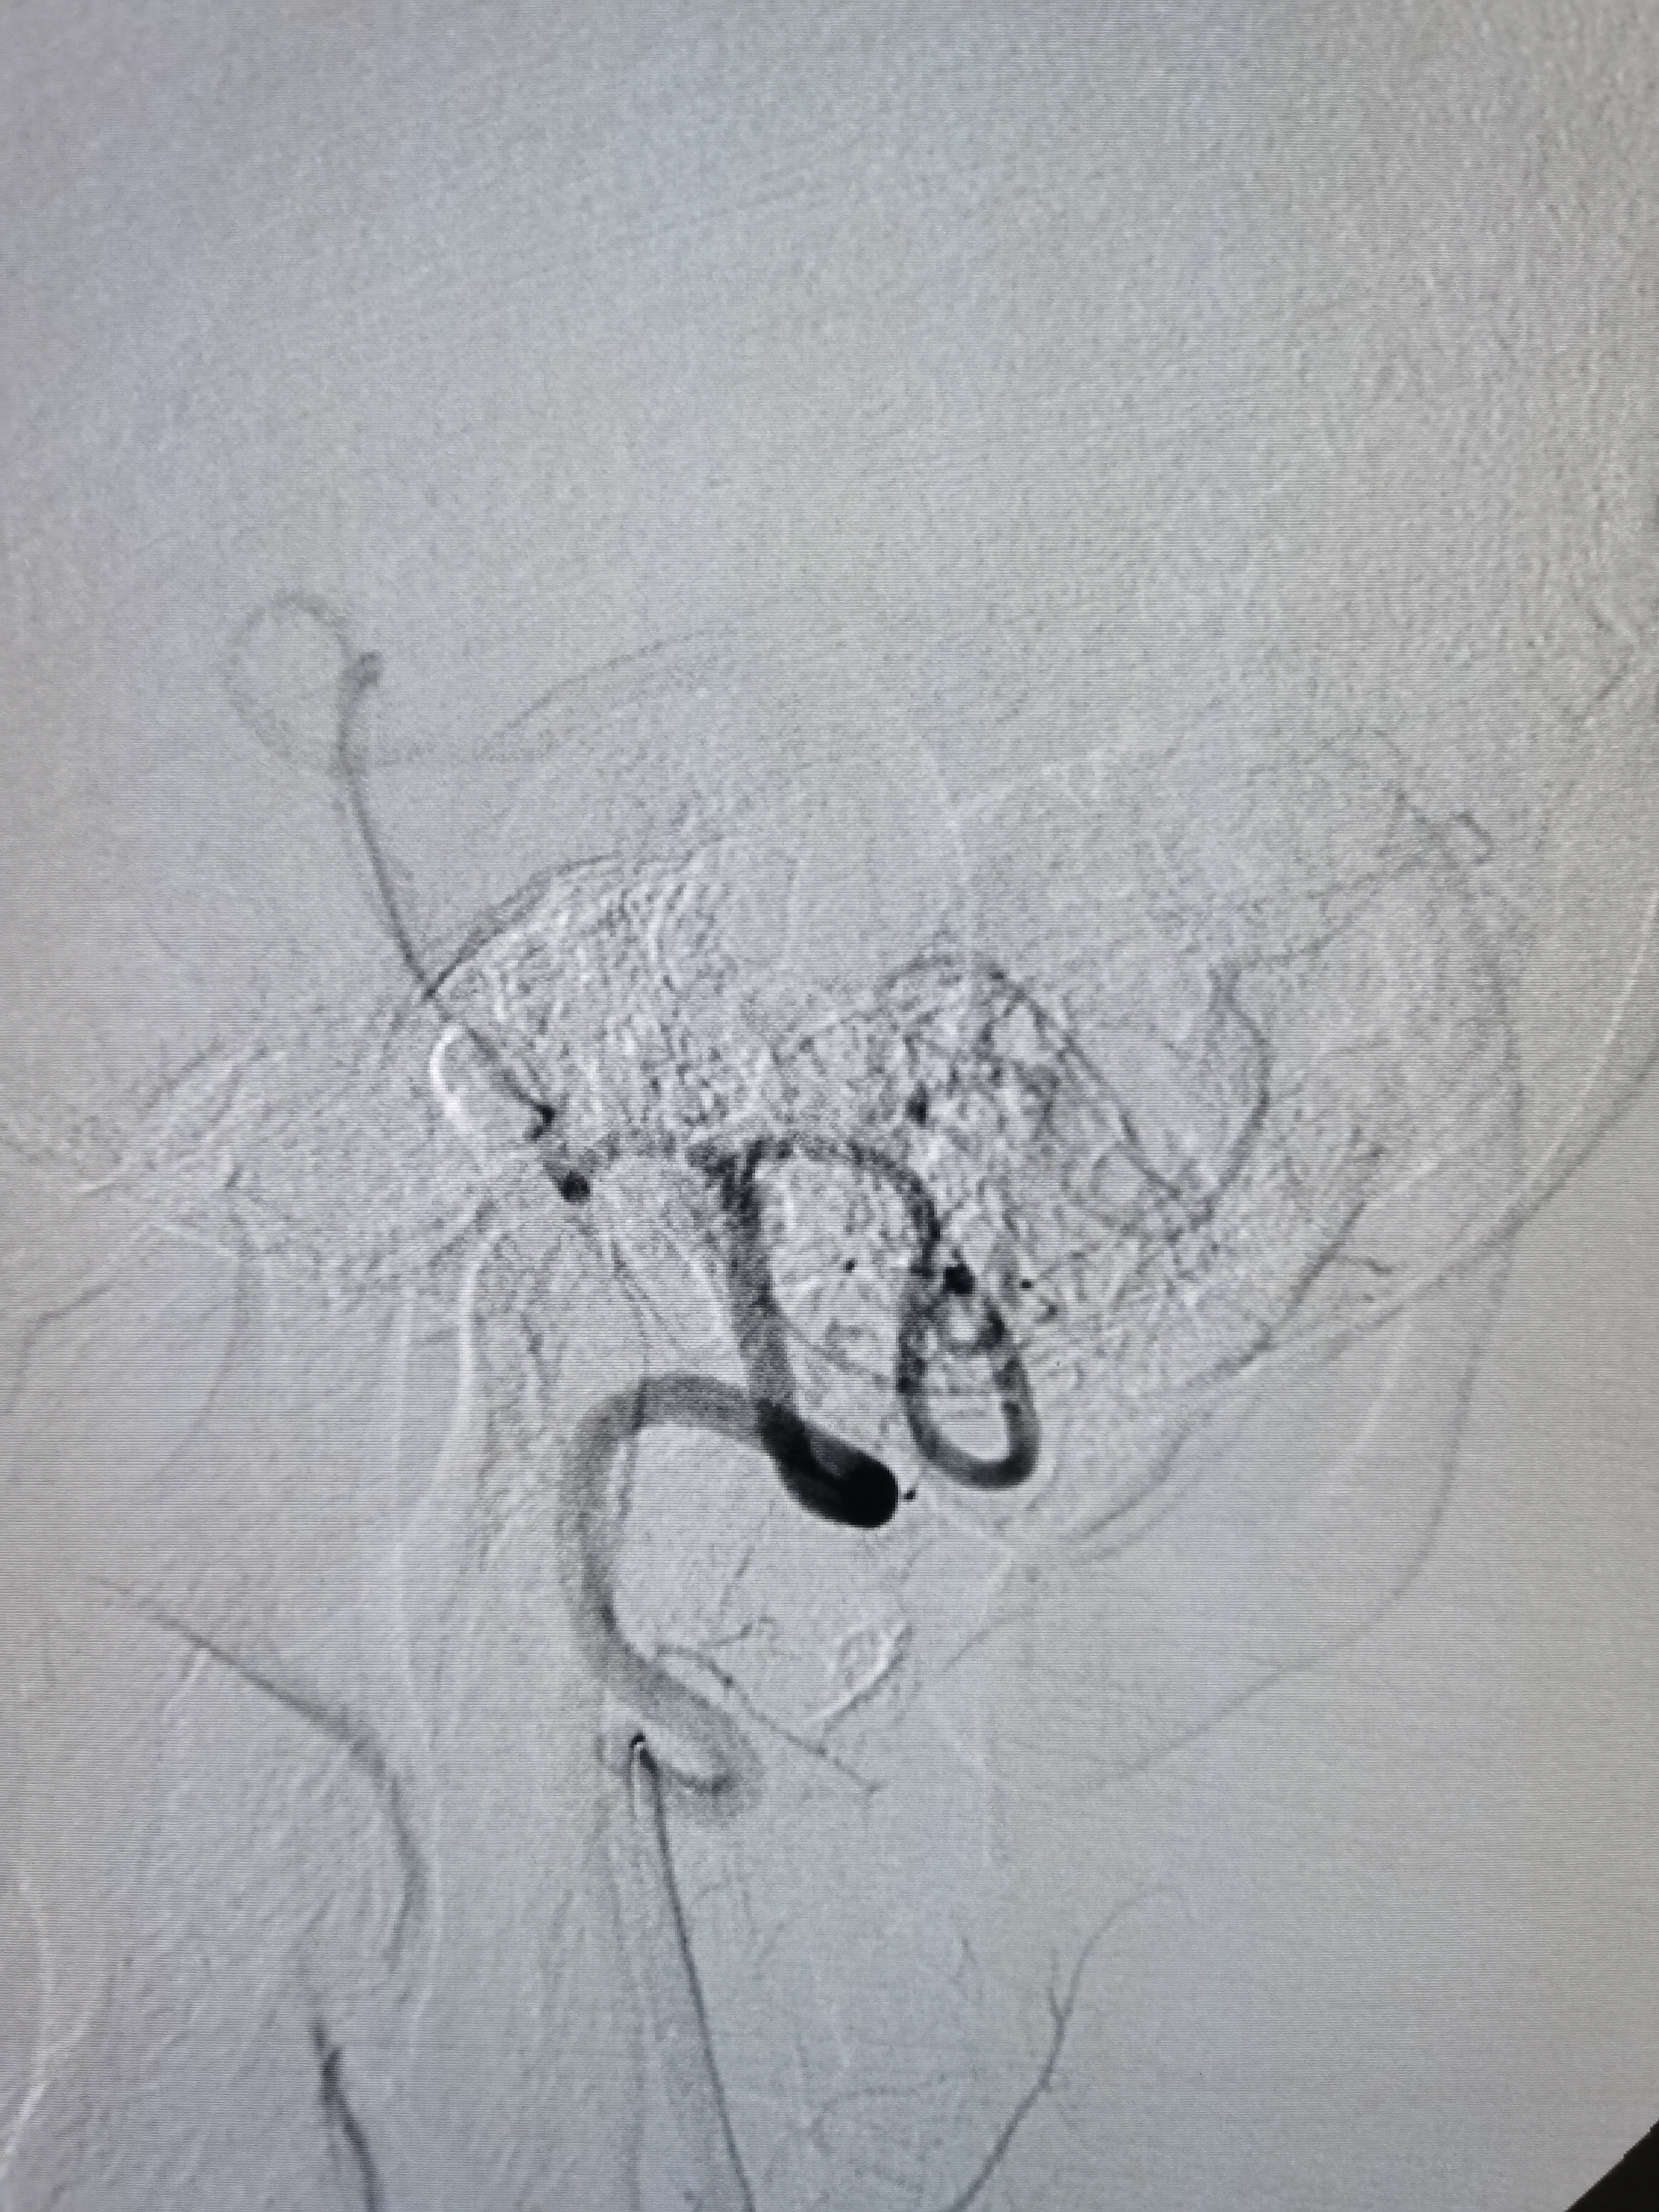

将8F导引导管送至左侧锁骨下动脉近左椎动脉起始部,微导丝顺利通过病变,2.0/20球囊预扩病变。

2、CTA证实左椎动脉起始部重度狭窄合并血栓,系责任血管,存在急性闭塞或残存血栓脱落至基底动脉风险,需积极处理。

3、手术过程中,先用小球囊扩张病变,观察血栓情况,及时应用支架全程覆盖血栓及病变部位,成形满意。